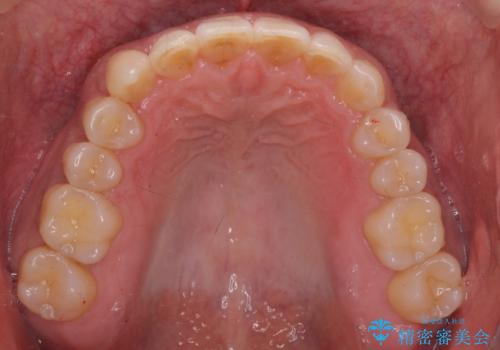

八重歯と下の歯のがたつき マウスピースで

- 右上の犬歯が目立つのが気になる、下の歯並びも治したいとのことで来院。

歯を抜かずに少し削って小さくして並べました。

並びも良くなり、患者様にも喜んでいただきました。

右上の犬歯の歯肉退縮自体は進行する可能性をお伝えしておりましたが、特に変化なく治療できました。

歯肉退縮につきましては、歯ぐきの移植を提案しましたが特に希望されませんでした。